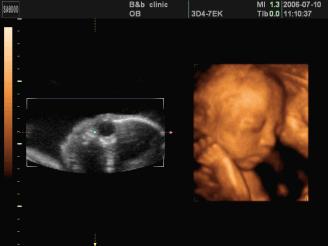

●四维彩超

四维彩超能够对胎儿进行动态、立体超声检查,显示胎儿的面部、各器官的发育情况,甚至胎儿在母体里的状态也可以观察到;对胎儿畸形,如唇裂、腭裂、骨骼发育异常等能早期诊断。另外还能制作成光盘,让宝宝拥有最完整的0岁相册,留下永久的记忆。

过去使用的B超设备只能检查胎儿的一些生理指标,而四维彩超还能对胎儿的体表进行检查,如唇裂,脊柱裂,大脑、肾、心脏、骨骼发育不良等情况,以便尽早的进行治疗,生个聪明健康的小宝宝。四维彩超能进行宫内写真,让准妈妈看到宫内宝宝的一举一动,亲身体会到宝宝的笑容相貌!而且四维彩超可以把宫内四维彩超宝宝的动态刻录成dvd作为宝宝的0岁写真!永久留念!